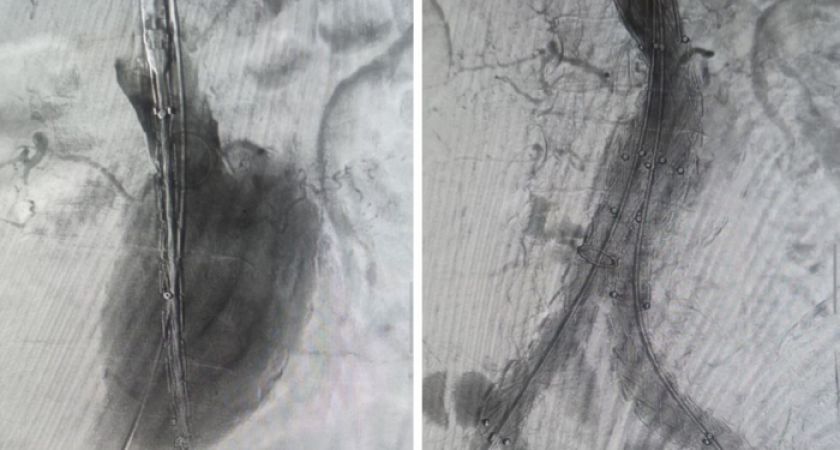

Вместо рискованного открытого вмешательства медики применили малотравматичный метод установки стент-графта, сообщили в облздраве.

Решение о выборе щадящей технологии было принято из-за сложного состояния пациента — мужчины старше 70 лет с крупной аневризмой и тяжелыми хроническими заболеваниями. Традиционная операция для него была сопряжена с высоким риском.

Специальная конструкция — стент-графт — была доставлена по сосудам и установлена внутрь аорты. Стент, представляющий собой прочный металлический каркас, создал новый канал для кровотока, а тканевая часть укрепила стенку сосуда, предотвратив ее разрыв. Это позволило избежать жизнеугрожающих осложнений.